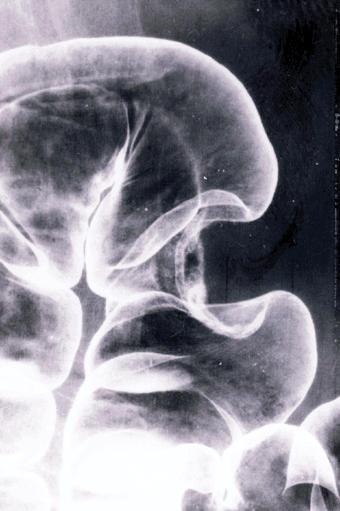

측면상에서 장관의 대형상변형을 보인 궤양국한형(2형) 진행대장암

[Image-ID:414]

악성 상피성종양/선암

대장/횡행

X-P

2형(궤양국한형)/

35~40

s(a)